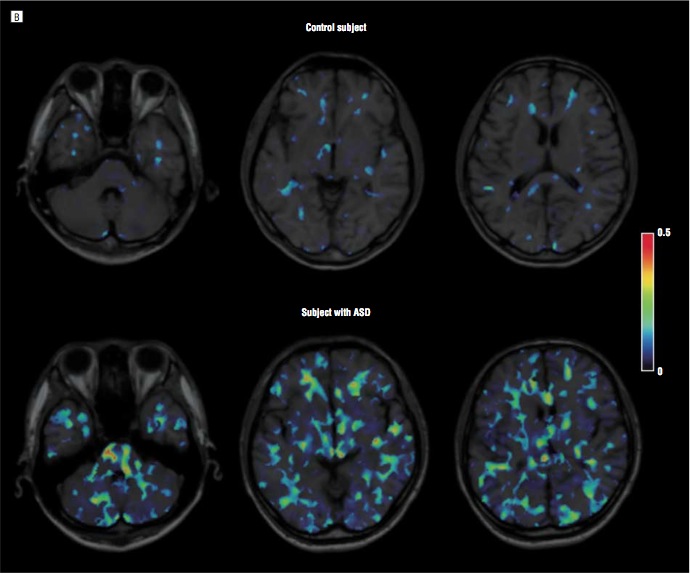

Today, the evidence for a chronic inflammation in the autistic brain is overwhelming. For example, in the following excellent study, brains of autistic and matched normal subjects were scanned for markers of microglial activation by positron emission tomography (PET). The autistic brains had widespread microglial activation throughout the brain.

Paper (Suzuki et al.): “Microglial Activation in Young Adults with Autism Spectrum Disorder”

Above: Positron emission tomography (PET) images of autistic subject and normal control. Colored areas indicate regions of microglial (immune) activation. Colored areas are “inflammatory lesions.” Dr. Paul Offit claims the colored areas in the autistic brain do not exist. Dr. Offit tells this lie because he knows the inflammatory lesions implicate vaccines as a cause of autism. From Suzuki et al.

ASD = Autism Spectrum Disorder.